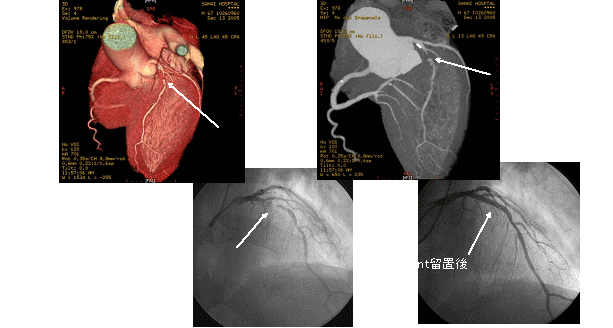

このボリュームCTにより早期発見から早期治療へつなげることが可能となり、心臓カテーテル検査の代替としても期待されます。

一部の症例以外では、従来の心臓カテーテル検査なしに血管狭窄の評価が可能であり、万が一、心筋梗塞になられた場合でも治療後の経過観察の心臓カテーテル検査は不要となります。